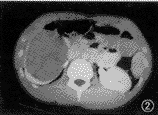

B超:右肾下极见一9.8 cm×8.4 cm×6.9 cm 的中等回声区,其内回声均匀,边界清楚,包膜完整,肾盂部分受侵。彩色多普勒超声显像(CDFI):肿物内部见点状血流。诊断:右肾下极实性占位,恶性肿瘤可能性大。CT检查:右肾中下极可见一巨大椭圆形肿块,边缘光滑,大小约10 cm×8 cm×8 cm ,其内密度较均匀,平扫时CT值为19~26 HU(图1),增强后为45~65 HU(图2),肾实质平扫时的CT值41.5 HU,增强后为145 HU。右肾后部实质弧形受压,肾盂变扁,向后内侧移位,肿块压迫下腔静脉向外移位。诊断:右肾中下极实性占位病变,肿瘤可能性大。

图2 增强后右肾实质均匀强化,病灶呈相对低密度区